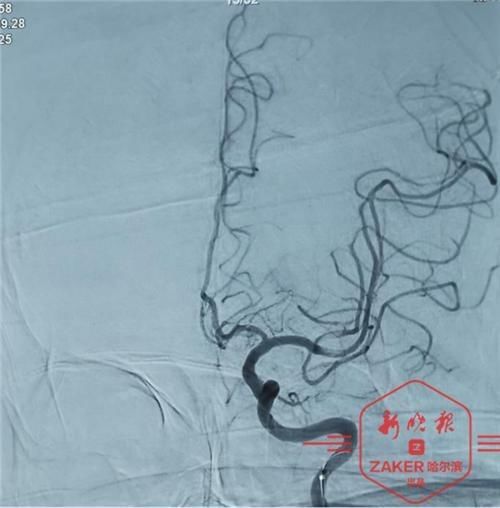

张先生今年 68 岁,清晨起来时,他突然感觉右侧肢体 " 不听使唤了 ",家人便赶紧带他来到哈医大四院就诊。途中,他突发昏迷,并频繁呕吐。到医院后,根据症状,神经外科李利教授判断他可能有颅内大血管闭塞。快速完成核酸检测后,医生紧急为张先生进行脑血管造影,发现他颈内动脉严重狭窄,且有斑块脱落,随时可能有生命危险,需要立即进行手术。

在导管室等科室的全力配合下,李利紧急为张先生进行手术治疗。术中,李利发现张先生左侧颈内动脉起始处狭窄严重,颈内动脉末端颅内血管未显影,脑动脉消失。在置入颈动脉支架,行远端闭塞处血管支架取栓治疗后,血管立刻恢复了正常血流。术后,张先生意识清楚,手脚也能正常活动了。